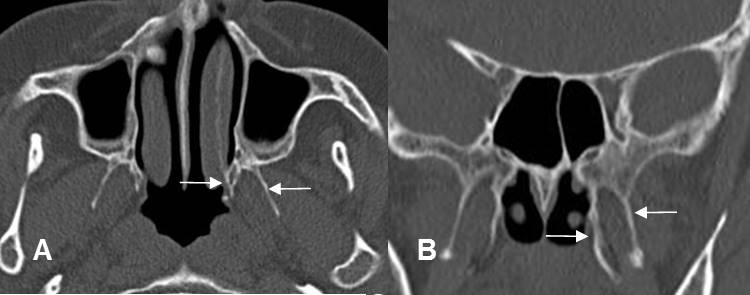

A: TAC axial y B: TAC reconstrucción coronal. Fractura en el borde interno de la órbita.

C: TAC axial en ventana de tejidos. Hay herniación de la grasa, pero permanece intacto el músculo recto interno.